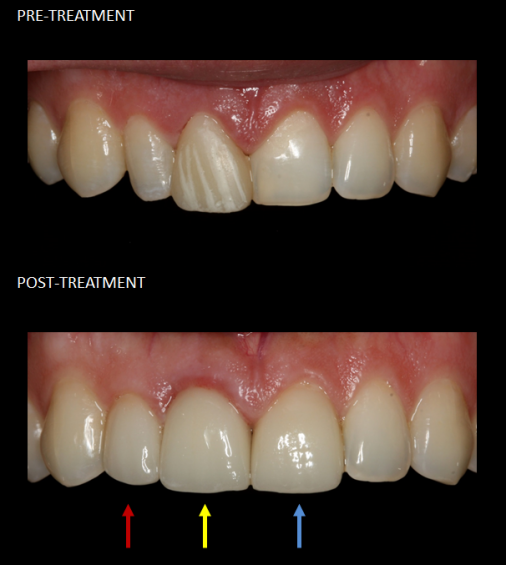

Restoration of front teeth with a crown (red), implant (yellow), and veneer (blue).